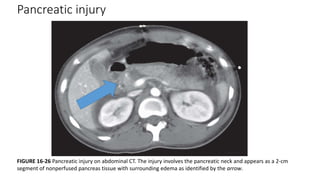

FIGURE 16-26 Pancreatic injury on abdominal CT. The injury involves the pancreatic neck and appears as a 2-cm

segment of nonperfused pancreas tissue with surrounding edema as identified by the arrow.